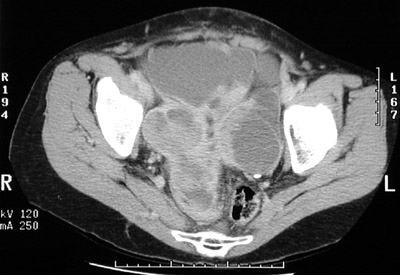

| The bilateral pelvic masses on the right and on the left have both cystic and solid components. They arise in the region of the ovaries. These proved to be serous cystadenocarcinomas of the ovaries. In the view above, there is adjacent small bowel filled with bright contrast. The view below, these bilateral neoplasms nearly fill the lower pelvis. |